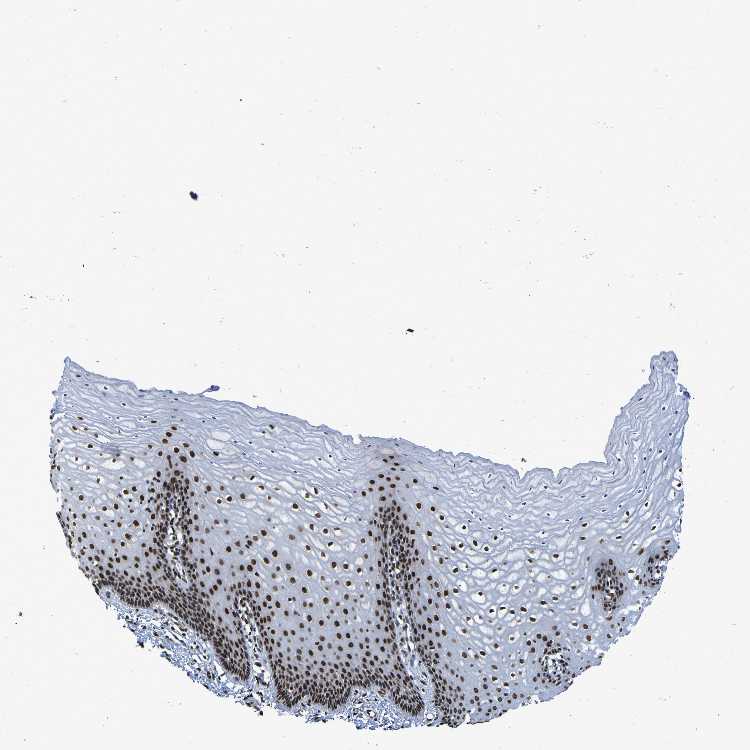

TISSUE PRIMARY DATA CERVIX Show tissue menu

CERVIX - Antibody stainingi

Antibody staining in the annotated cell types in the current human tissue is reported as not detected, low, medium, or high, based on conventional immunohistochemistry profiling in selected tissues. This score is based on the combination of the staining intensity and fraction of stained cells.

Each image is clickable and will lead to virtual microscopy that enables deeper exploration of all samples and also displays staining intensity scores, fraction scores and subcellular localization as well as patient and tissue information for each sample.

Antibody HPA026092Antibody CAB011687

Glandular cells MediumHigh

Squamous epithelial cells MediumHigh